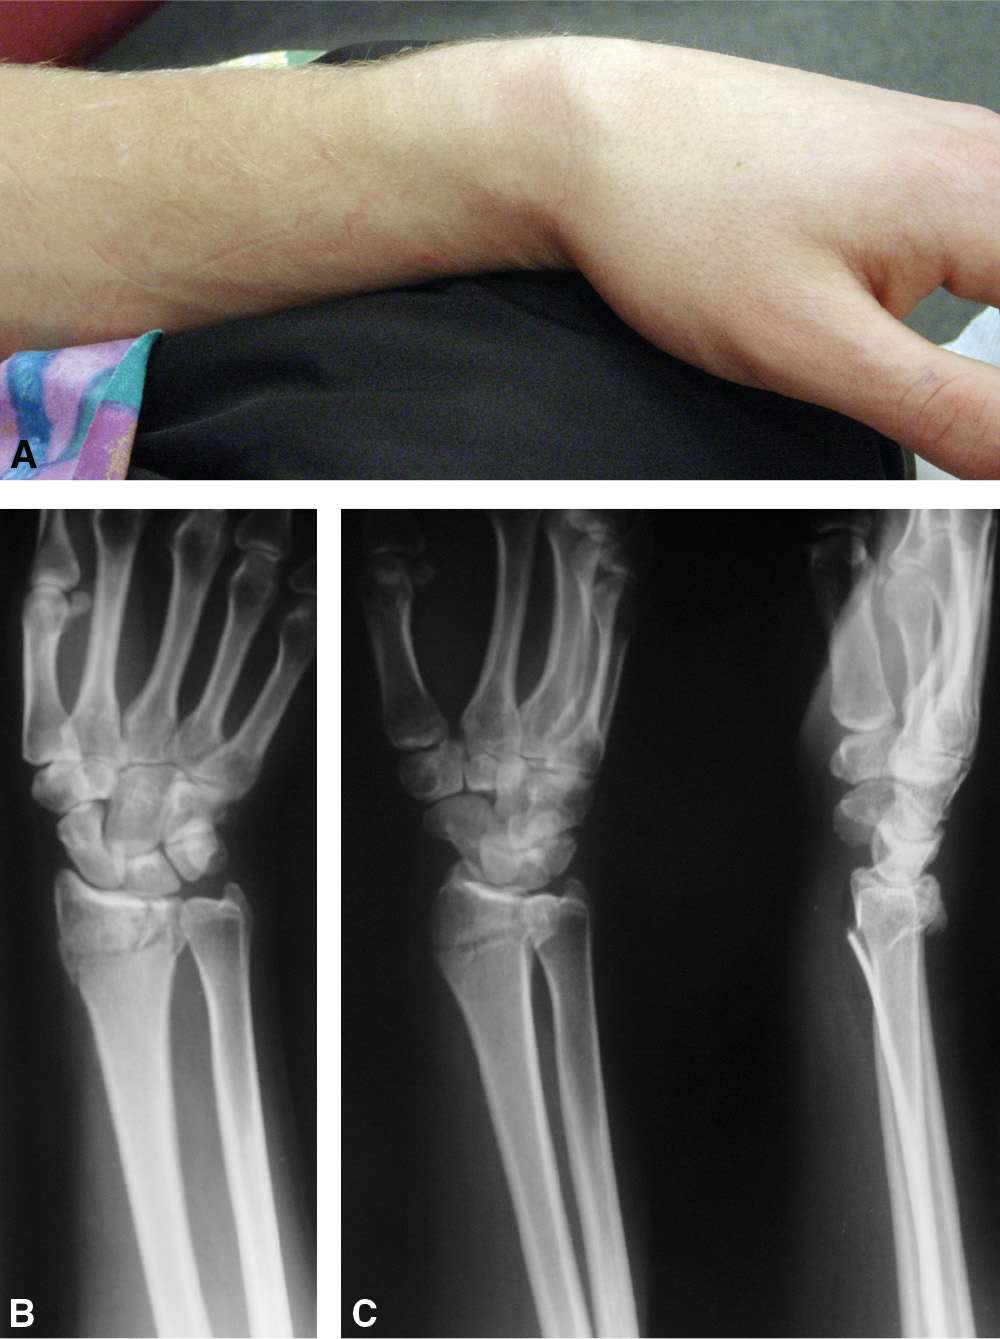

Обращаться за профессиональной помощью к специалистам необходимо при появлении следующих признаков появления перелома лучезапястного сустава:

- Сильная и резкая боль в области запястья, кисти и предплечья.

- Отёчность и гематомы в области запястья.

- Невозможность свободных движений в нижних отделах руки.

- Аномальная подвижность костей.

- Повышение температуры в месте повреждения.

- Характерный хруст в процессе получения травмы.

- Внешняя деформация руки.

- При открытом переломе свободно просматриваются обломки кости и сухожилия.

В каждом отдельном случае точный перечень симптоматики и её интенсивность будет определяться индивидуально в зависимости от особенностей конкретной ситуации и полученной травмы. Но при этом обязательно следует обращаться за помощью к докторам. А также могут быть отягчающие факторы в виде смещения, проявления осколков, повреждения мягких тканей. Только доктор проведёт соответствующее обследование, поставит точный диагноз и составит дальнейший план лечения и реабилитации. Только при таком подходе можно достичь выздоровления и избежать многочисленных осложнений. А для скорейшего выздоровления в Новотитаровской следует обращаться к специалистам частного центра реабилитации «Исток».